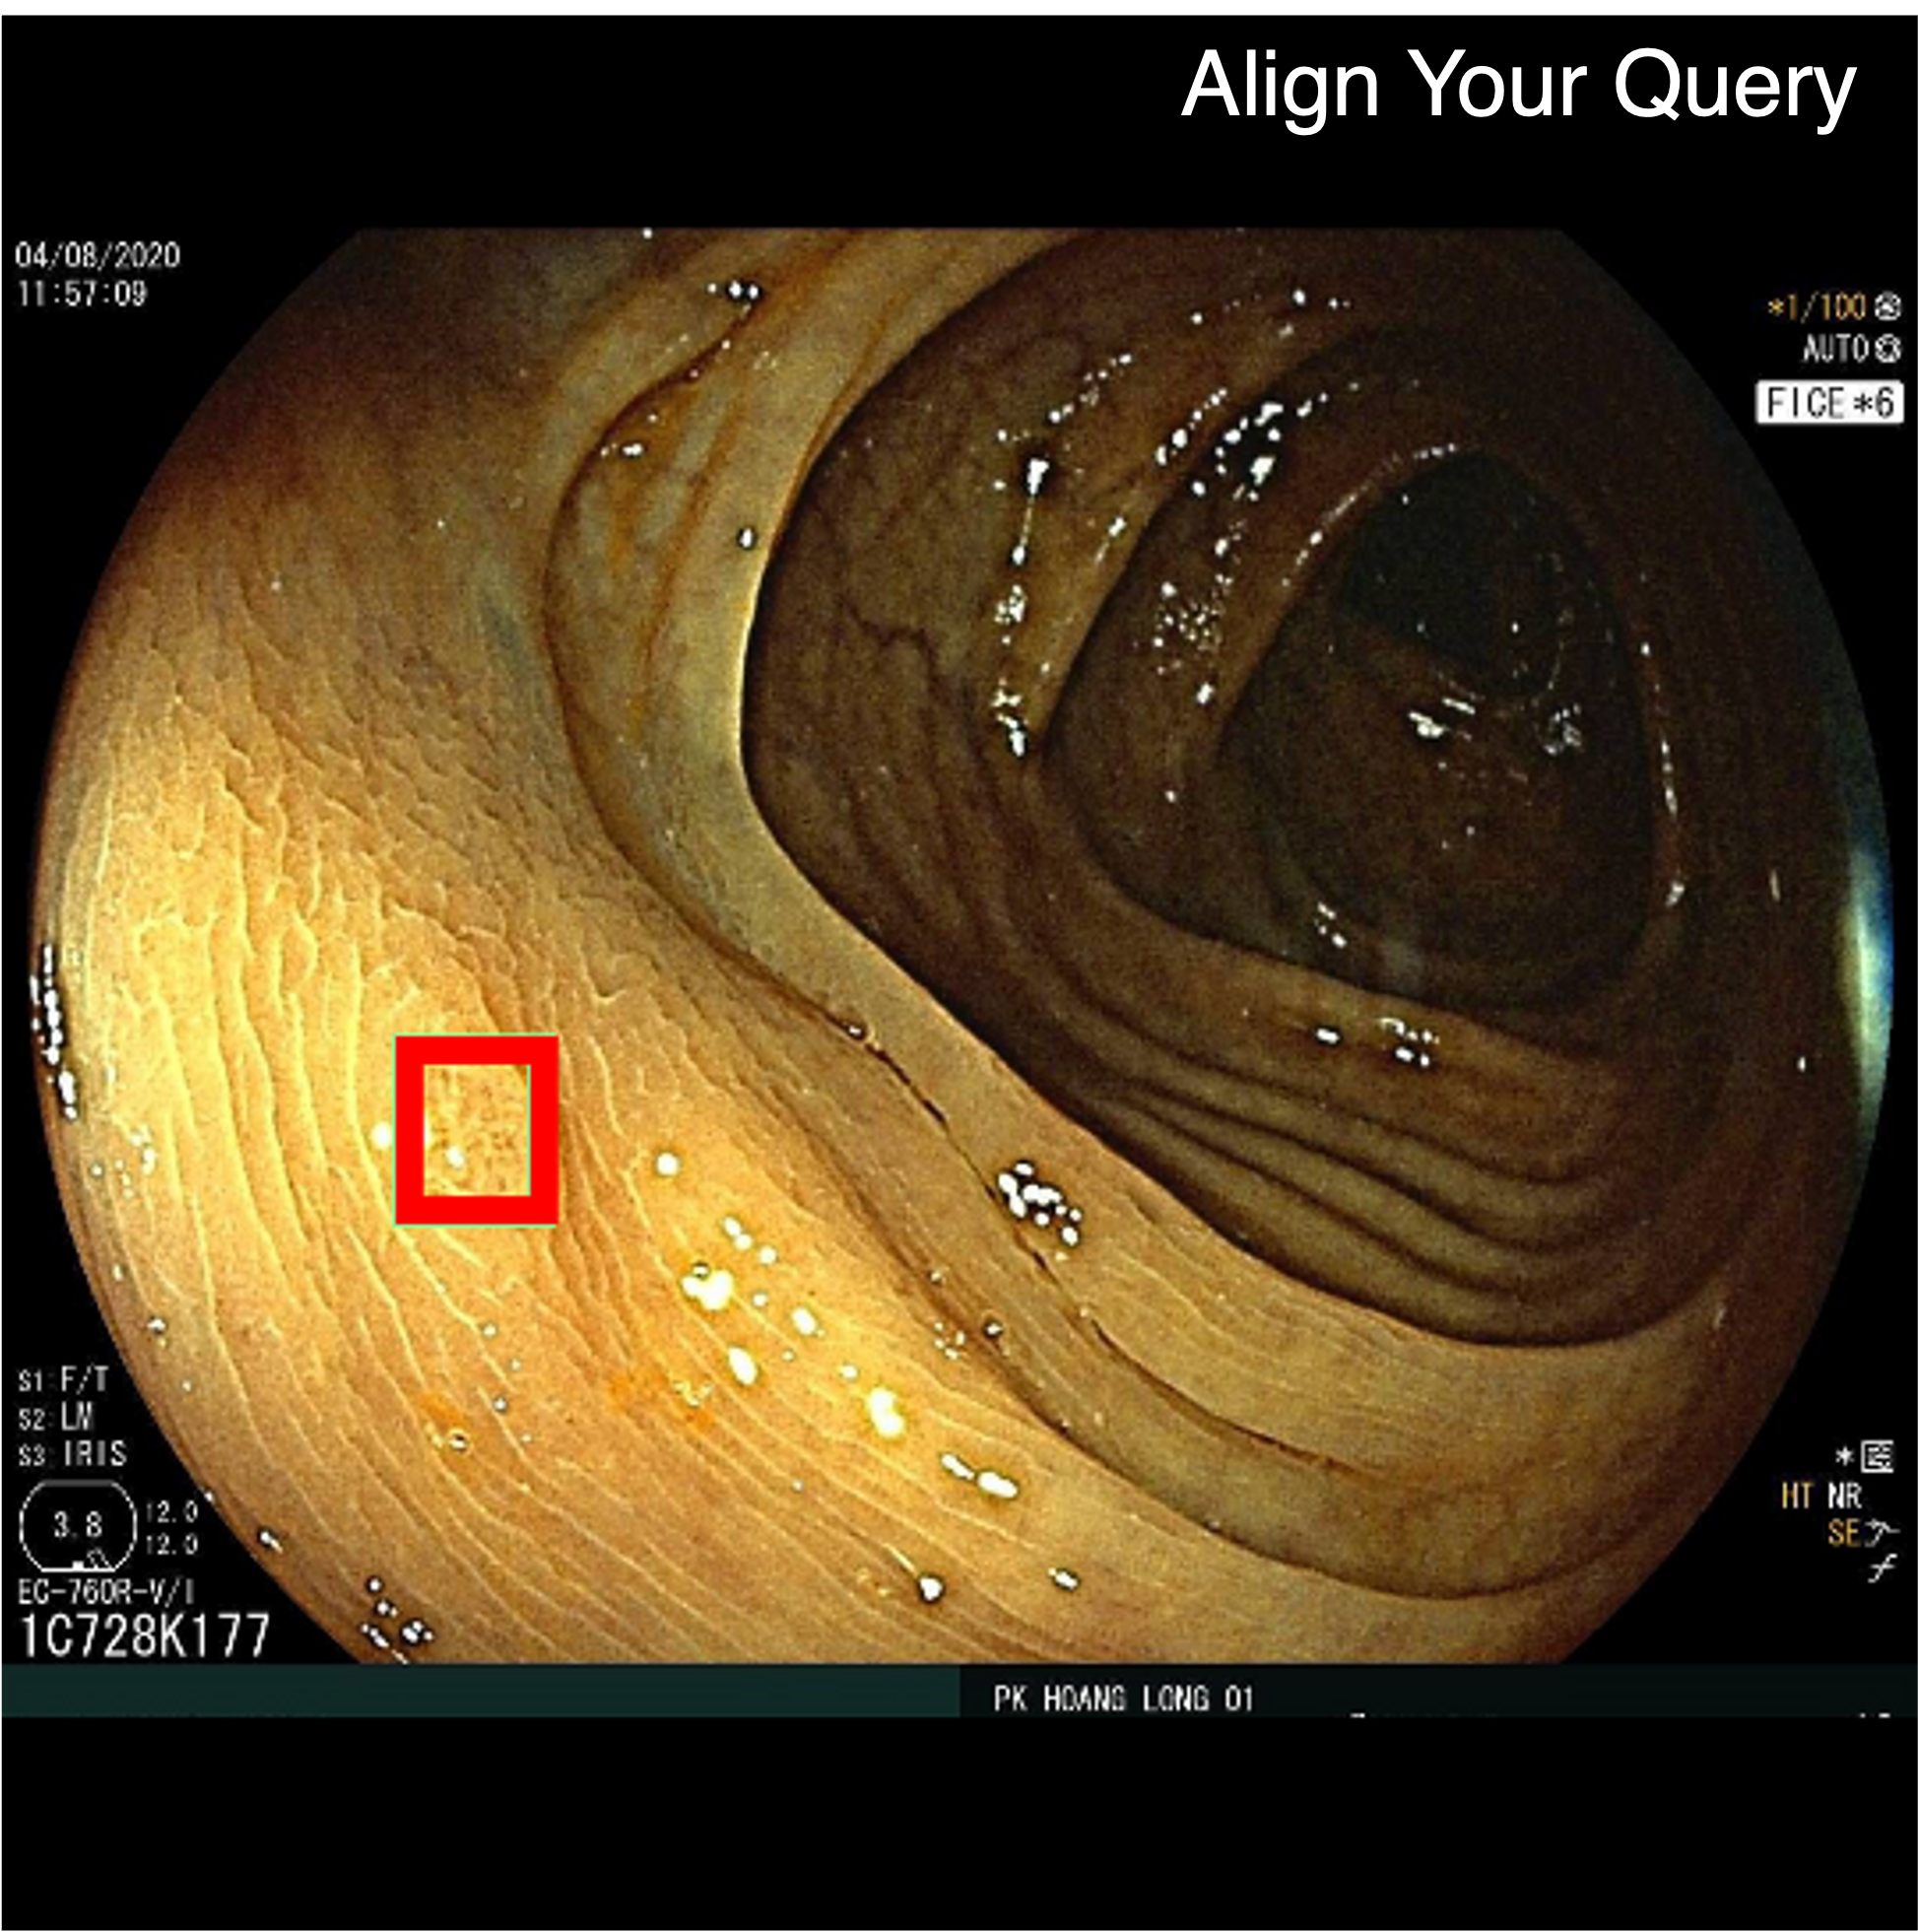

Qualitative comparison results

Qualitative Comparison. Comparison results between various state-of-the-art detection methods and the proposed method is shown above. Our method effectively leverages modality context to significantly enhance anomaly localization (red), compared to baseline results (blue). Ground truth bounding boxes are green. For cases where the bounding boxes are small, insets show an enlarged view of the highlighted yellow region.